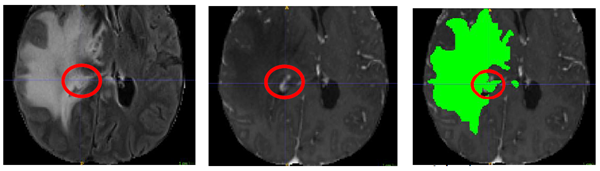

Specifically for Task 1 (Tumor sub-region segmentation), all imaging volumes have then been segmented using the STAPLE [25] fusion of previous top-ranked BraTS algorithms, namely, nnU-Net [26], DeepScan [27], and DeepMedic [28]. These fused labels were then refined manually by volunteer neuroradiology experts of varying rank and experience, following a consistently communicated annotation protocol. The manually refined annotations were finally approved by experienced board-certified attending neuro-radiologists, with more than 15 years of experience working with gliomas. The annotated tumor sub-regions are based upon known observations visible to the trained radiologist (VASARI features) and comprise the Gd-enhancing tumor (ET — label 4), the peritumoral edematous/invaded tissue (ED — label 2), and the necrotic tumor core (NCR — label 1). ET is the enhancing portion of the tumor, described by areas with both visually avid, as well as faint, enhancement on T1Gd MRI. NCR is the necrotic core of the tumor, the appearance of which is hypointense on T1Gd MRI. ED is the peritumoral edematous and infiltrated tissue, defined by the abnormal hyperintense signal envelope on the T2 FLAIR volumes, which includes the infiltrative non enhancing tumor, as well as vasogenic edema in the peritumoral region. The tumor sub-regions are shown in Fig. 1.

Refer to caption

Figure 1: Glioma sub-regions considered in the RSNA-ASNR-MICCAI BraTS 2021 challenge. Image panels with the tumor sub-regions annotated in the different mpMRI scans. The image panels A-C denote the regions considered for the performance evaluation of the participating algorithms and specifically highlight (from left to right): the enhancing tumor (ET - yellow) visible in a T1Gd scan, surrounding the cystic/necrotic components of the core (panel A), the tumor core (TC – magenta) and the whole tumor (WT - cyan) visible in the corresponding T2 (panel B) and T2-FLAIR (panel C) scans, respectively. Panel D, depicts the combined segmentations generating the final tumor sub-region labels, as provided to the BraTS 2021 participants: enhancing core (yellow), necrotic/cystic core (red), and edema/invasion (green).

We designed the following tumor annotation protocol, to ensure consistency in the ground truth delineations across various annotators. For the tasks related to BraTS, only structural mpMRI volumes were considered (T1, T1Gd, T2, T2-FLAIR), all of them co-registered to a common anatomical template (SRI24 [18]) and resampled to 1mm3. The end to end pipeline is available for these through CaPTk [19, 20, 21] and FeTS tools. We note that radiologic definition of tumor boundaries, especially in such infiltrative tumors as gliomas, is a well-known problem. In an attempt to offer a standardized approach to assess and evaluate various tumor sub-regions, the BraTS initiative, after consultation with internationally recognized expert neuroradiologists, defined the various tumor sub-regions. However, we note that other criteria for delineation could be set, resulting in slightly different tumor sub-regions. For the BraTS 2021 challenge the regions considered are: i) the “enhancing tumor” (ET), ii) the “tumor core” (TC) and iii) the complete tumor extent also referred to as the “whole tumor” (WT). The ET is described by areas that show hyper-intensity in T1Gd when compared to T1, but also when compared to “healthy” white matter in T1Gd. The TC describes the bulk of the tumor, which is what is typically considered for surgical excision. The TC entails the ET, as well as the necrotic (NCR) parts of the tumor, the appearance of which is typically hypo-intense in T1Gd when compared to T1. The WT describes the complete extent of the disease, as it entails the TC and the peritumoral edematous/invaded tissue (ED), which is typically depicted by the abnormal hyper-intense signal in the T2-FLAIR volume.